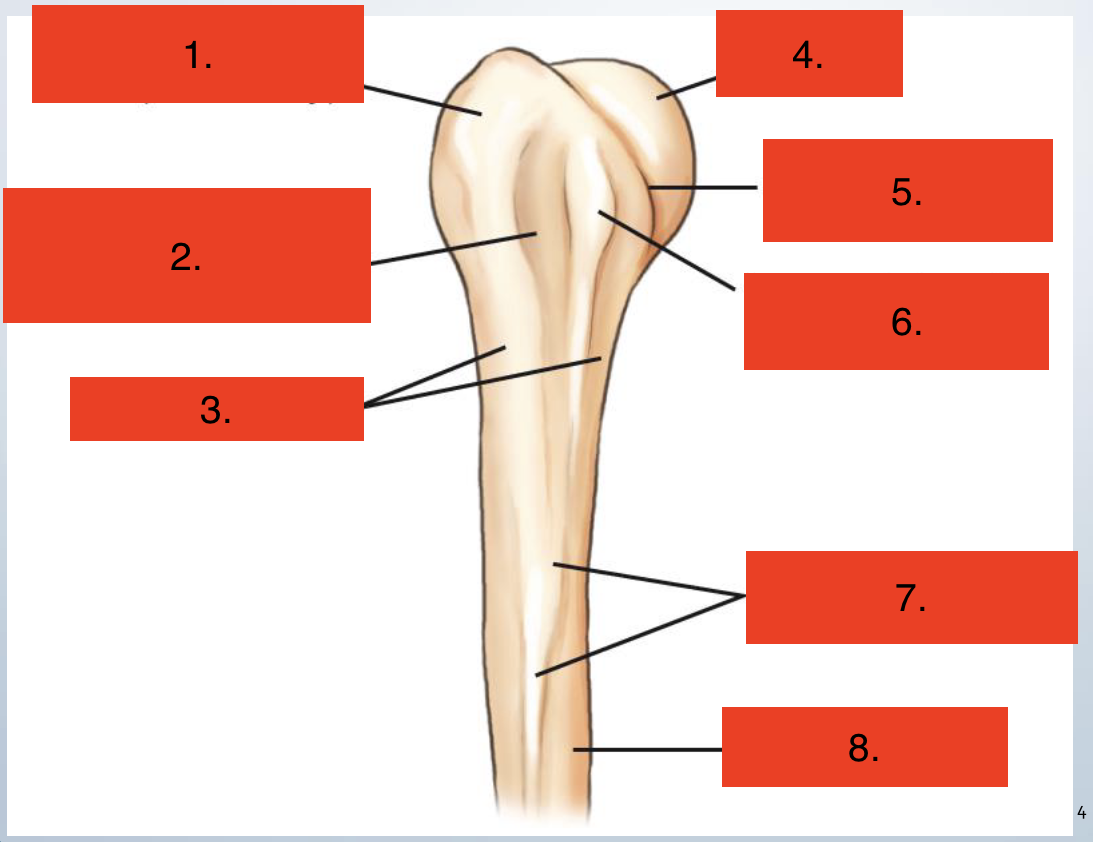

Proximal Humerus

Greater Tubercle

Intertublar groove

Surgical neck

Head

Anatomic neck

Lesser tubercle

Deltoid Tuberosity

Body